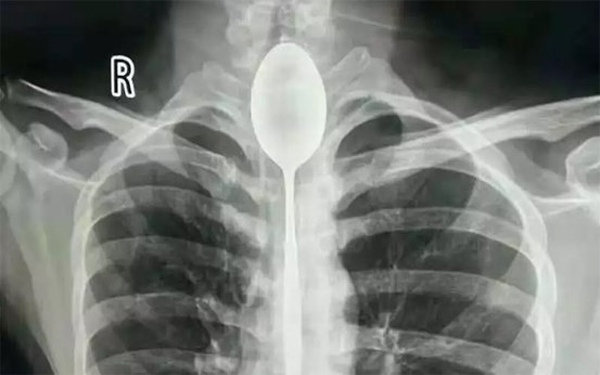

3. Người đàn ông bị một cái muỗng bị mắc kẹt trong thực quản

Một người đàn ông ở Trung Quốc cảm thấy đau ngực và khó thở nên đã đến bệnh viện khám. Hình chụp X-quang cho thấy có một chiếc thìa bị mắc kẹt trong thực quản của anh từ một năm trước. Nhưng đáng ngạc nhiên, chiếc thìa không gây ra cho anh ấy nhiều sự khó chịu.

Các bác sĩ đã thực hiện một thủ tục kéo dài hai giờ để lấy thìa ra, theo một tuyên bố từ Bệnh viện Đa khoa Tân Cương Meikuang, nơi bệnh nhân được điều trị vào tháng 10.